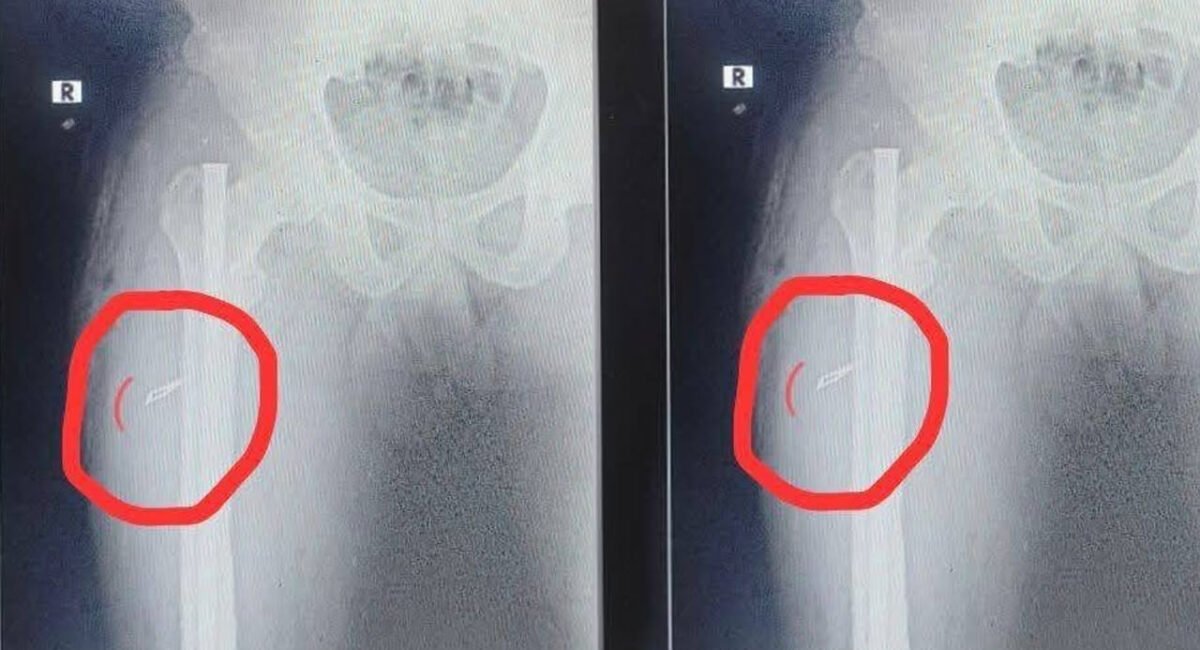

స్టెరాయిడ్స్ విక్రయాలు తిడుతున్న వ్యవహారం పోలీసుల దృష్టికి రావడంతో వరంగల్ లోని మట్టవాడ పోలీసులు శ్రవణ్ ను అదుపులోకి తీసుకొని విచారణ జరిపారు. వియత్నం, జర్మనీ, బల్గేరియా దేశాల నుండి వీటిని ఆన్ లైన్ లో దిగుమతి చేసుకుంటున్నట్లు పోలీసుల గుర్తించారు. మణికంఠ, ఆనంద్ ఆన్లైన్లో కొనుగోలు చేస్తున్నట్లు పోలీసులు గుర్తించారు. ప్రస్తుతం ఒకరిని అరెస్టు చేసిన పోలీసులు పరారీలో ఉన్న మరో ముగ్గురి కోసం గాలిస్తున్నారు. ఇలాంటి స్టెరాయిడ్స్ వినియోగించినా, విక్రయాలు జరిపివా వారిపై కఠిన చర్యలు ఉంటాయని హెచ్చరికలు జారీ చేశారు. వీరి వద్ద భారీ ఎత్తున స్టెరాయిడ్స్ ఇంజక్షన్లు, టాబ్లెట్స్ స్వాధీనం చేసుకున్నారు.